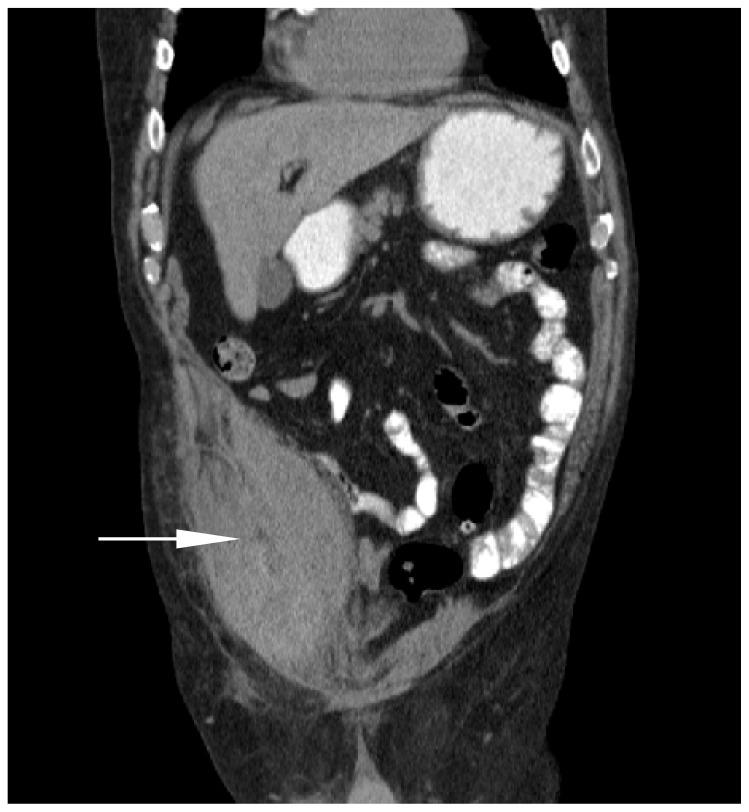

Rectus sheath hematoma: an unfortunate consequence of novel anticoagulants.